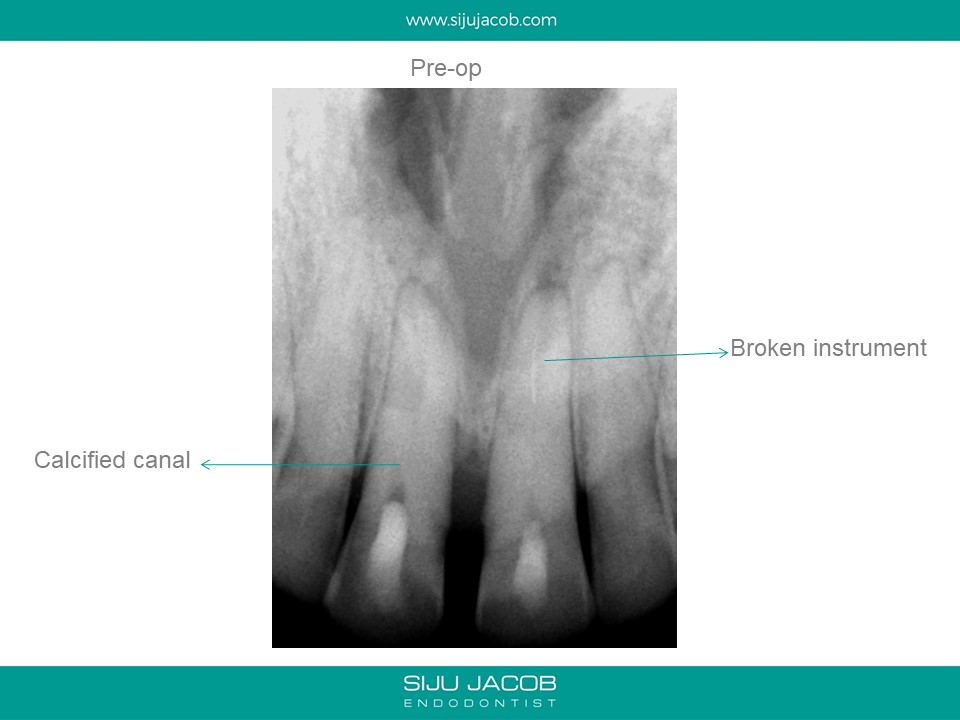

This was a case which was started by another clinican. A Naso-palatine cyst was mis-diagnosed as lesion of endodontic origin. The clinician opened up two central incisors, broke an instrument in one, couldn’t locate the canal (nearly perforated) and then referred the case.